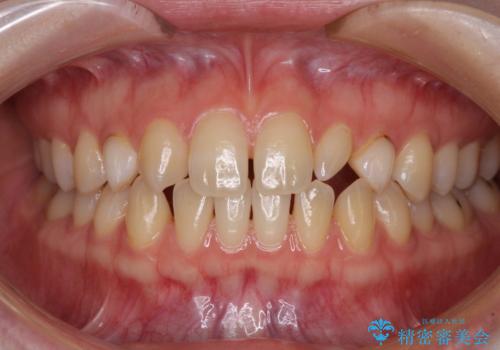

- 前歯の奇形や欠損、乳歯残存などによる審美障害を気にして来院された患者様です。

正中の隙間は矯正治療により閉じ、左右の4歯はオールセラミッククラウンにて補綴することとしました。